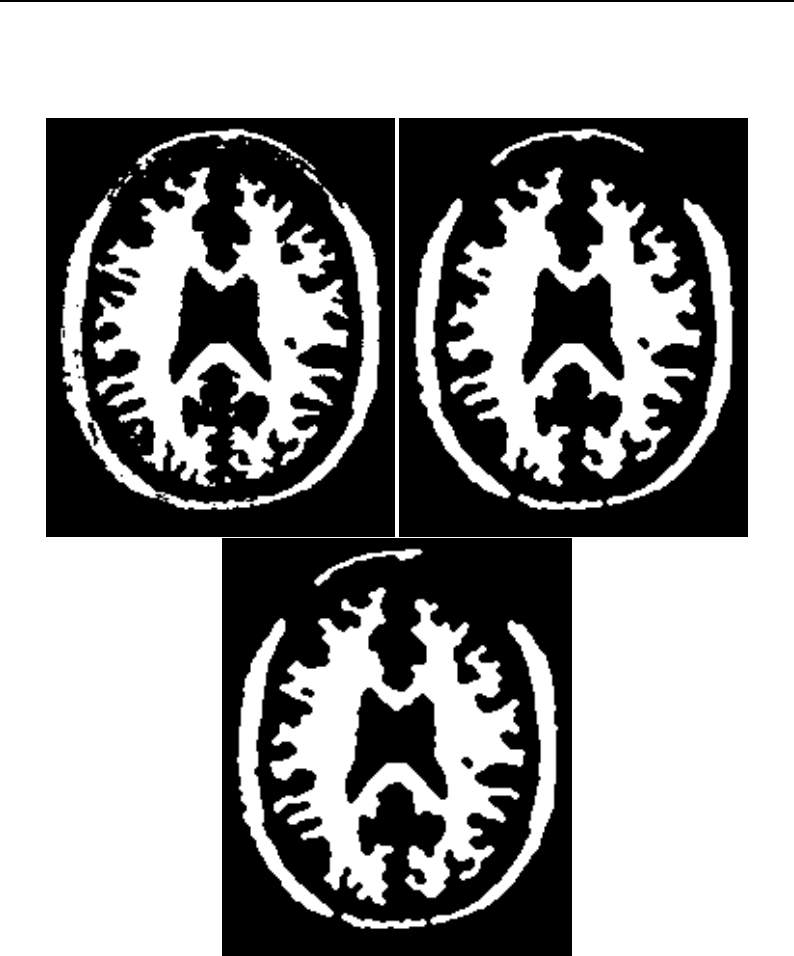

The Insight Toolkit (ITK) is an open-source, cross-platform system for medical image processing. It

provides medical imaging researchers with an extensive suite of leading-edge algorithms for

registering, segmenting, analyzing, and quantifying medical data. It is used in thousands of research

and commercial applications, from major labs to individual innovators.

The National Library of Medicine Insight Segmentation and Registration Toolkit, shortened as the

Insight Toolkit (ITK), is an open-source software toolkit for performing registration and segmenta-

tion. Segmentation is the process of identifying and classifying data found in a digitally sampled

representation. Typically the sampled representation is an image acquired from such medical instru-

mentation as CT or MRI scanners. Registration is the task of aligning or developing correspondences

between data. For example, in the medical environment, a CT scan may be aligned with a MRI scan

in order to combine the information contained in both.